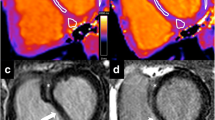

Visualization of longitudinal contribution to stroke volume. Cardiac magnetic resonance images in four-chamber view. A Solid lines represent the atrioventricular (AV) plane at end diastole, and B dashed lines represent the atrioventricular plane at end systole. The end-systolic line is interpolated to the end-diastolic image. The AV-plane displacement is the distance between the solid line in end diastole and the dashed line in end systole as shown to the left. The longitudinal contribution to stroke volume is computed as the volume encompassed by the AV-plane displacement, here illustrated with blue color in the left ventricle and green color in the right ventricle. (Color figure online)

The SVlat% and SVsept% were calculated from the delineated epicardial contours of the free LV and RV walls as well as the septal wall. The RV insertion points were used to define the extent of the septum (Fig. 3A). Due to longitudinal shortening of the ventricles the basal slices only have the septum in diastole, and therefore only slices with ventricular septum present in both end diastole and end systole were used for calculation of lateral and septal contributions to SV. The lateral SV was calculated as the area between the epicardial border at end diastole and end systole multiplied by slice thickness, including slice gap, summed for all included slices. The SVlat% was computed by dividing this volume by the total SV for the respective ventricle, generating LV-SVlat% and RV-SVlat% (Fig. 3). The septal SV was calculated as the area between the septal border at end diastole and end systole multiplied by slice thickness, for all included slices (Fig. 3). The SVsept% was defined as septal SV divided by LV-SV. Positive SVsept% was defined as septal contribution to LV-SV and negative as contribution to RV-SV.

CMR images in short axis view. A Solid lines represent the epicardial borders and black circles RV insertions points at end diastole, and B dashed lines represent the epicardial borders at end systole. The end diastolic contour is interpolated to the end-systolic image. The area between the solid and dashed lines inside the RV insertion points (purple area, panel B) represents the septal contribution to stroke volume, which was summed from all short-axis slices. The area between the solid and dashed lines outside of the RV insertion points represent the lateral contribution to stroke volume, which was summed from all short-axis slices (green area, lateral contribution to RV, blue area lateral contribution to left ventricle). (Color figure online)